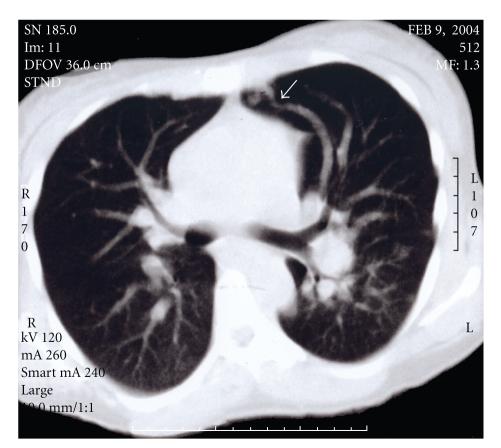

High-output cardiac failure secondary to hepatic involvement is a rare complication of hereditary hemorrhagic telangiectasia (HHT). Here we report a 43-year-old woman who presented at 29 weeks gestation of her second pregnancy with complications of right-sided heart failure and preterm labor. After delivery via cesarean section, the patient was found to have intrahepatic arteriovenous malformations through non-invasive imaging. Subsequently, a family history of vascular malformations and epistaxis was elucidated and a diagnosis of HHT was made. This case is presented, along with a review of the literature and discussion of hepatic involvement in HHT with particular focus on the pregnant patient.

继发于肝脏受累的高输出性心力衰竭是遗传性出血性毛细血管扩张症(HHT)的罕见并发症。我们在此报告了一位 43 岁的女性,她在第二次妊娠 29 周时因右侧心力衰竭和早产并发症就诊。经剖宫产分娩后,通过无创影像学检查发现患者存在肝内动静脉畸形。随后,发现存在血管畸形和鼻出血的家族史,并诊断为 HHT。本文呈现了该病例,并对文献进行了回顾,讨论了 HHT 中的肝脏受累,特别关注了孕妇患者。